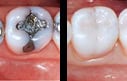

อินเลย์และออนเลย์ เป็นการบูรณะฟันอีกรูปแบบหนึ่ง มักใช้สำหรับอุดทดแทนเนื้อฟันที่เสียหายไปมากกว่า40 %ของเนื้อฟัน 1ซี่ โดยการทำการบูรณะแบบ อินเลย์ออนเลย์นี้ มีทั้งแบบใช้วัสดุอุดเรซินสีเหมือนฟัน วัสดุชนิดเซรามิก ทอง และเงิน มาขึ้นรูปเป็นชิ้นงานนอกช่องปาก แล้วนำชิ้นงานนั้นๆไปยึดติดในรูฟันที่กรอเตรียมไว้แล้ว ด้วยซีเมนต์ทางทันตกรรม การอุดฟันด้วยวิธีนี้จะแข็งแรงมากกว่าการอุดแบบธรรมดา

Amalgam filler เป็นวัสดุชนิดโลหะ สีเงิน ใช้สำหรับอุดฟันที่ต้องการความแข็งแรง หรือเมื่อทันตแพทย์พิจารณาแล้วว่า ไม่สามารถหรือไม่สมควรที่จะอุดด้วยวัสดุสีขาวมุกได้ โดยทั่วไปมักใช้อุดฟันกรามที่ต้องการความแข็งแรงสูง เพื่อใช้ในการบดเคี้ยว หรือบริเวณที่เข้าทำความสะอาดยาก เป็นต้น